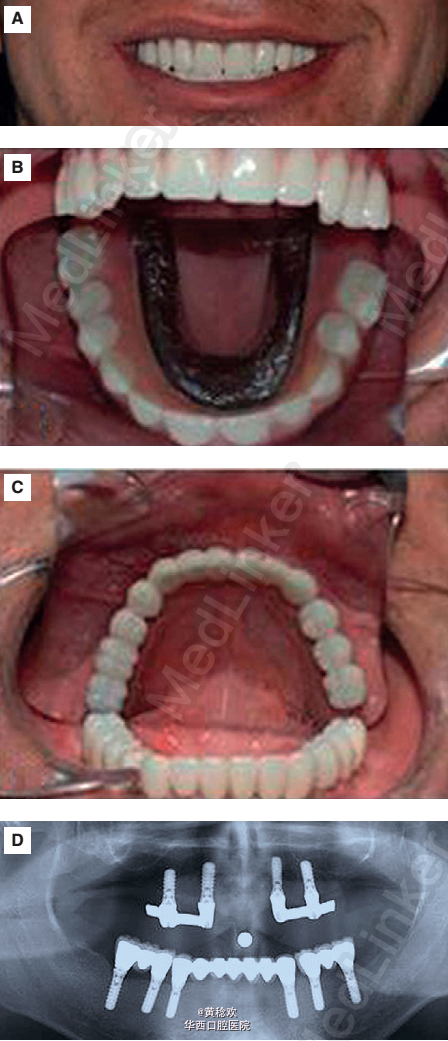

牙本质发育不良是一种罕见的常染色体显性遗传疾病(发病率1:100000),牙本质形成受阻,在临床上通常表现为临床牙冠正常,但通过放射检查可见牙根形态不良甚至没有牙根,无髓室腔,根周有无任何诱因的透射影。牙本质发育不良可分为I型和II型,前者更常见,表现为有乳牙和恒牙,牙冠正常,但牙根退化或无牙根,在牙釉质牙本质界可见一水平的放射投射影线,根尖周有透射影或囊肿。II型特点为牙根形态轮廓正常,部分牙髓闭塞,不定形的牙本质可形成髓石,长梗漏斗样牙髓室腔,线状根管,通常无根尖周透射影。因为牙齿缺乏正常牙根形态,很难通过临床上常规的操作将其移动排齐。 今日为大家分享一例因为牙本质发育不良I型的病人行全口种植修复的案例。